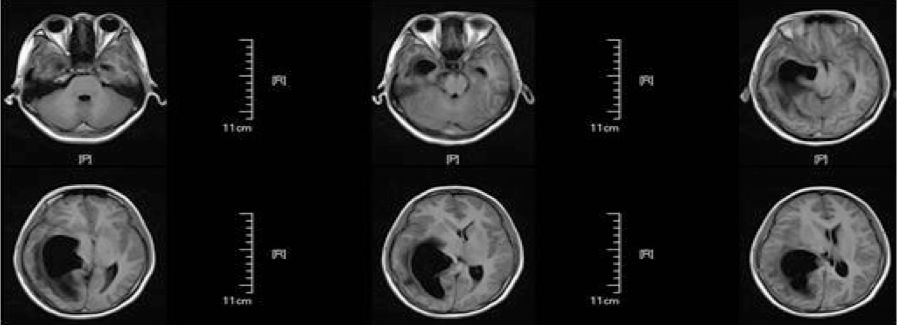

患者第一次肿瘤切除术后第1天复查头部CT无脑积水,于术后第4天拔出脑室外引流管,术后第14天复查头部MRI无异常(图2),后出院。术后第48天患者常规复查头部MRI(图3)提示右侧侧脑室颞角、后角扩张并周围脑组织水肿、中线轻度移位,由于患者无明显颅高压症状,予以观察并定期复查。患者于术后第62天开始出现头痛,恶心,在当地医院行甘露醇脱水治疗,治疗后症状稍改善,但停用脱水药物时患者头痛恶心呕吐症状就再出现。

图2. 术后第14天复查头部MRI无异常。

图3. 术后第48天患者常规复查头部MRI,提示右侧侧脑室颞角、后角扩张并周围脑组织水肿、中线轻度移位。